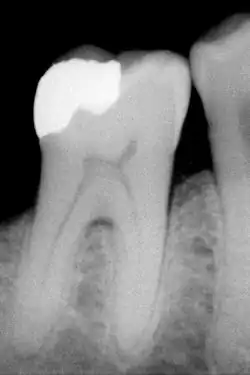

The large amount of mineral in enamel accounts not only for its strength but also for its brittleness.[6] Tooth enamel ranks 5 on Mohs hardness scale (between steel and titanium) and has a Young's modulus of 83 GPa.[4] Dentin, less mineralized and less brittle, 3–4 in hardness, compensates for enamel and is necessary as a support.[7] On radiographs, the differences in the mineralization of different portions of the tooth and surrounding periodontium can be noted; enamel appears lighter than dentin or pulp since it is denser than both and more radiopaque.[8]

An X-ray showing enamel and dentin replaced by an amalgam restoration